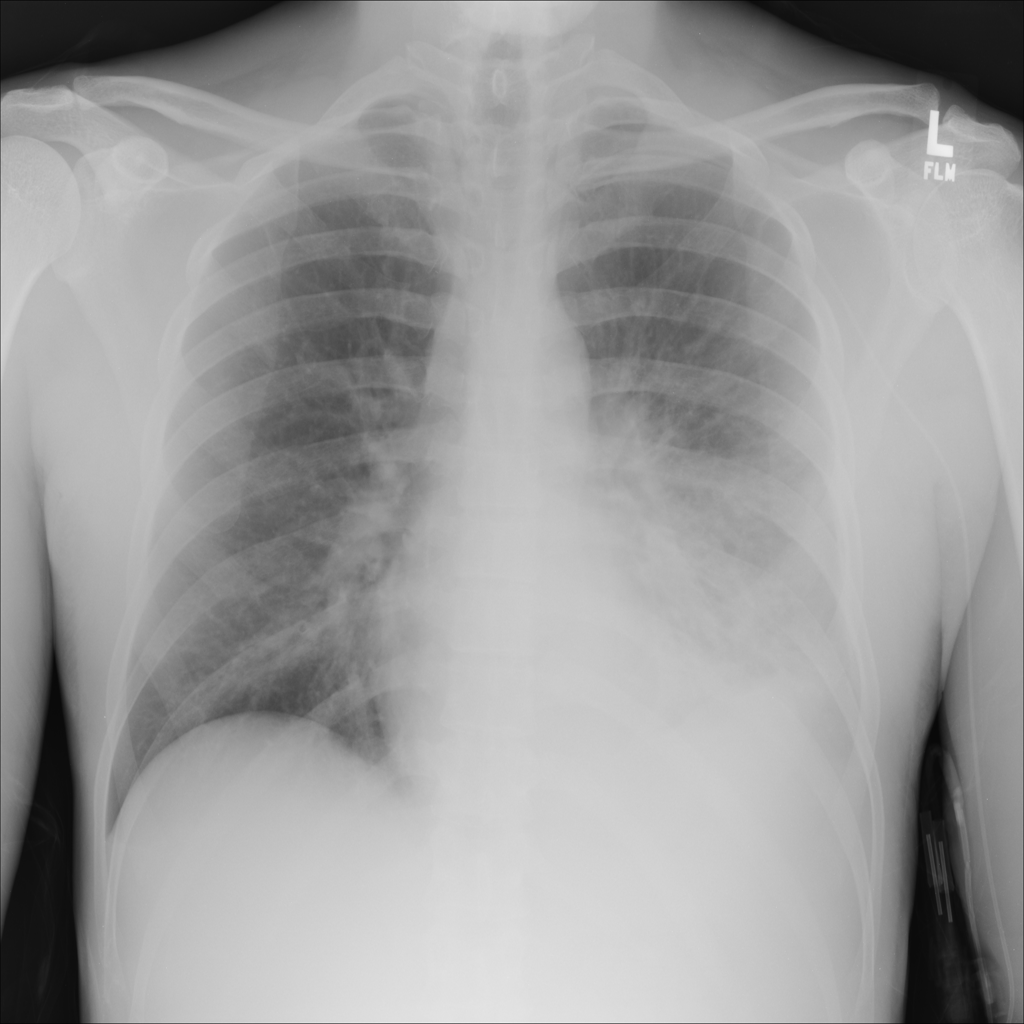

PAT-B3C3 · IMG-001Pneumonia

PAT-B3C3 · IMG-001

PA